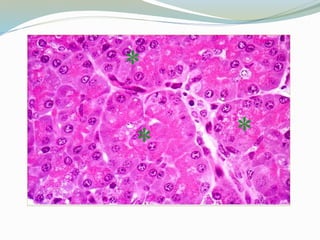

ESTÓMAGO  2 a3 L  Esfínter esofagogástrico o cardias  Esfínter pilórico  Pliegues o arrugas longitudinales  El alimento llega al estómago en forma de bolo y sale de el en forma de quimo  Jugo gástrico:  Ácido clorhídrico, enzimas (pepsina, renina y lipasa) y moco  Factor intrínseco  Gastrina